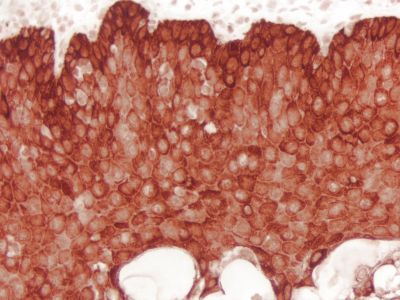

The peroxidase micropolymers of the ImmPRESS HRP polymer reagent limit steric interference and provide enhanced accessibility to the target, avoiding the disadvantages of other polymer systems that use large dextrans or other macromolecules as backbones. The result is crisp, strong staining of antibody targets, especially nuclear and membrane antigens (such as Ki67, estrogen receptor, bcl-2, CD3, CD8 and CD10) and greater sensitivity than other polymer systems.

The staining procedure is simple as shown in the diagram below. Following a blocking step with the diluted normal horse serum, sections are incubated with primary antibody. After a brief wash, the appropriate ImmPRESS Reagent is added to the sections and incubated for 30 minutes. Sections are again rinsed and the slides are developed with the peroxidase substrate of choice.